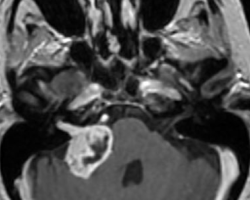

Un homme de 55 ans, n’ayant aucun antécédent personnel est envoyé pour réaliser une IRM par son ORL pour exploration d’acouphènes associés à une hypoacousie droite ainsi que des vertiges et une paralysie faciale périphérique droite d’apparition récente.